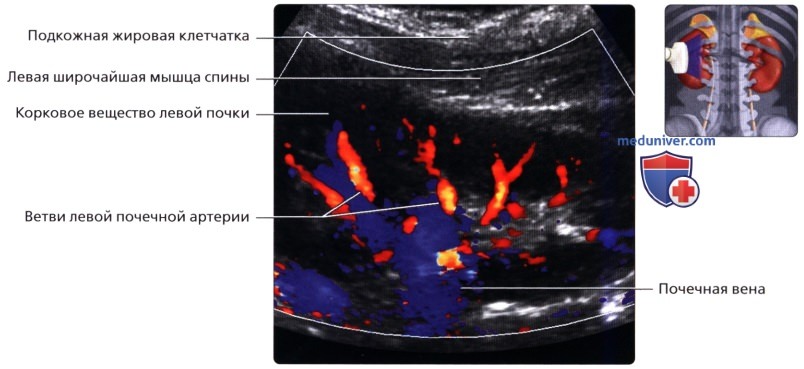

Неотъемлемой частью обследования почек стало ультразвуковое допплерографическое исследование, дающее возможность наблюдать за кровотоком в почечных сосудах. Делая УЗИ сосудов почек, можно установить на ранней стадии стеноз артерий, сбои в кровоснабжении, сосудистые сбои.

УЗДГ (УЗИ сосудов почек) выполняется в положении больного лежа на боку или сидя. Каких-то особенностей у этой процедуры нет. Врач также перемещает датчик по поверхности кожи пациента, внимательно изучая постоянно меняющиеся на мониторе изображения.

б) Лучевая анатомия почки:

1. Обзор:

• Забрюшинные структуры бобовидной формы с четким контуром, смещающиеся при дыхании

• Почечные артерии:

о Места отхождения лучше всего визуализируются при сканировании по срединной линии спереди

о Правую почечную артерию обычно можно проследить от места отхождения до почки

о Для визуализации левой почечной артерии часто требуется установить датчик на заднебоковой поверхности во фронтальной проекции

• Почечные вены:

о Лучше всего визуализируются при поперечном трансабдоминальном сканировании

о Также могут быть видны при сканировании в фронтальной плоскости с заднебоковой поверхности

Ультразвуковое исследование при заболеваниях сосудов почечного кровообращения

К этим заболеваниям относятся поражения почечной вены и артерий. Это могут быть сужения (стенозы), закупорка тромбом (тромбозы), а также нарушение целостности сосудов при травмах.